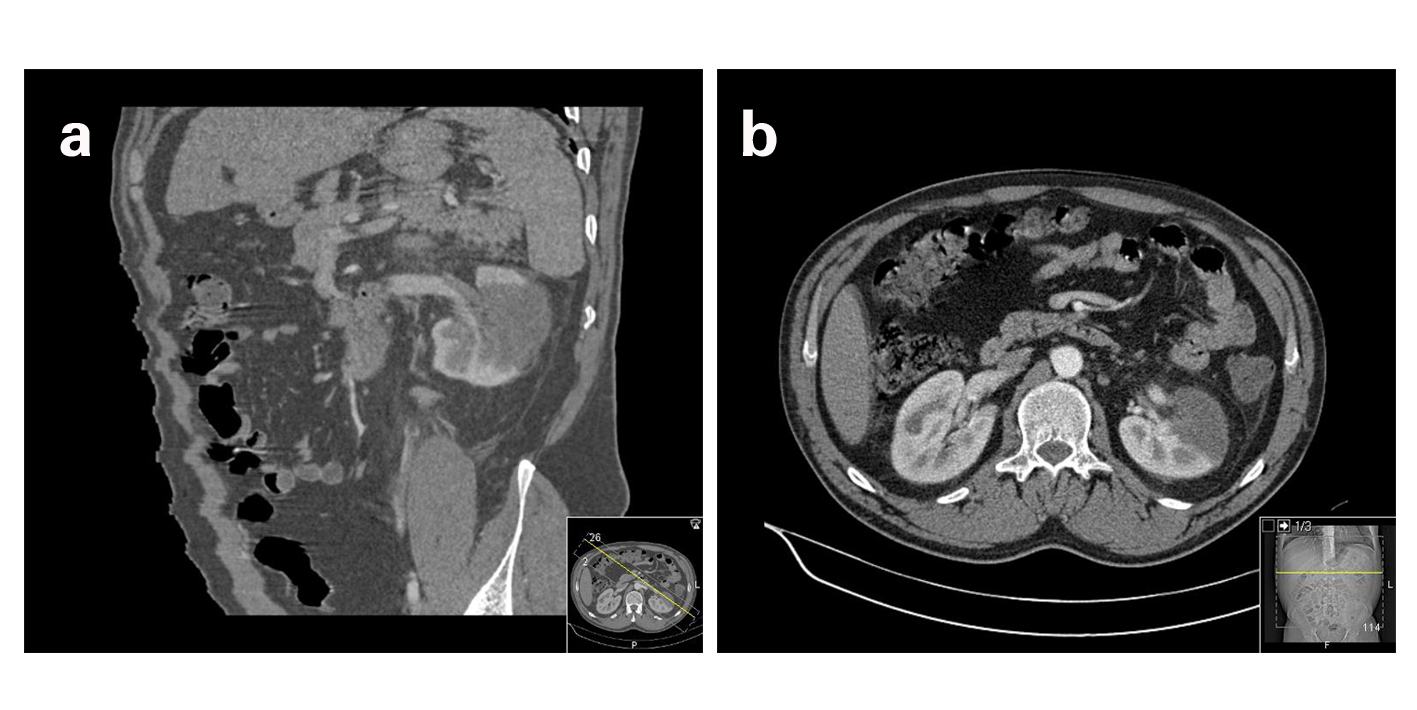

The patient was reassessed 2 days later for aggravation of algic complaints, refractory to the analgesics initially prescribed. Reevaluation of blood analysis presented normal hemogram and normal hepatic and renal function, although a slight elevation of LDH (398 U/L). CECT demonstrated absence of contrast uptake in the inferior pole and external surface of the left kidney due to the occlusion of a branch of the left renal artery (Fig. 3a, b). Given the course of evolution, the patient was initiated on low molecular weight heparin in therapeutic dosage (enoxaparin 80 mg twice daily). The etiologic study by CT angiography, echocardiogram, ECG, auto-immune and prothrombotic assay (factor V Leiden, lupus anticoagulant, protein C and S, anticardiolipin, antiphospholipid, antinuclear and antineutrophil cytoplasmatic antibodies) was negative. The genetic study for thrombophilia was also negative. The renal arteriography didn’t reveal stenosis, dissection or aneurysm of the renal artery or its main branches, presenting however slow progression of contrast in the inferior pole and absence of uptake in the more peripheral segments. The patient progressed uneventfully, without algic complaints since the second day of admission. The patient was discharged at the 14th day treated with anti-platelet aggregation and guided to follow up in Urology consult.

![]() Click for large image | Figure 3. a) CT angiography reconstruction showing infarction of a large area of the left kidney due to occlusion of a left renal artery branch. b) Abdominal CT revealing absence of contrast enhancement of the anterior portion of the left kidney. |